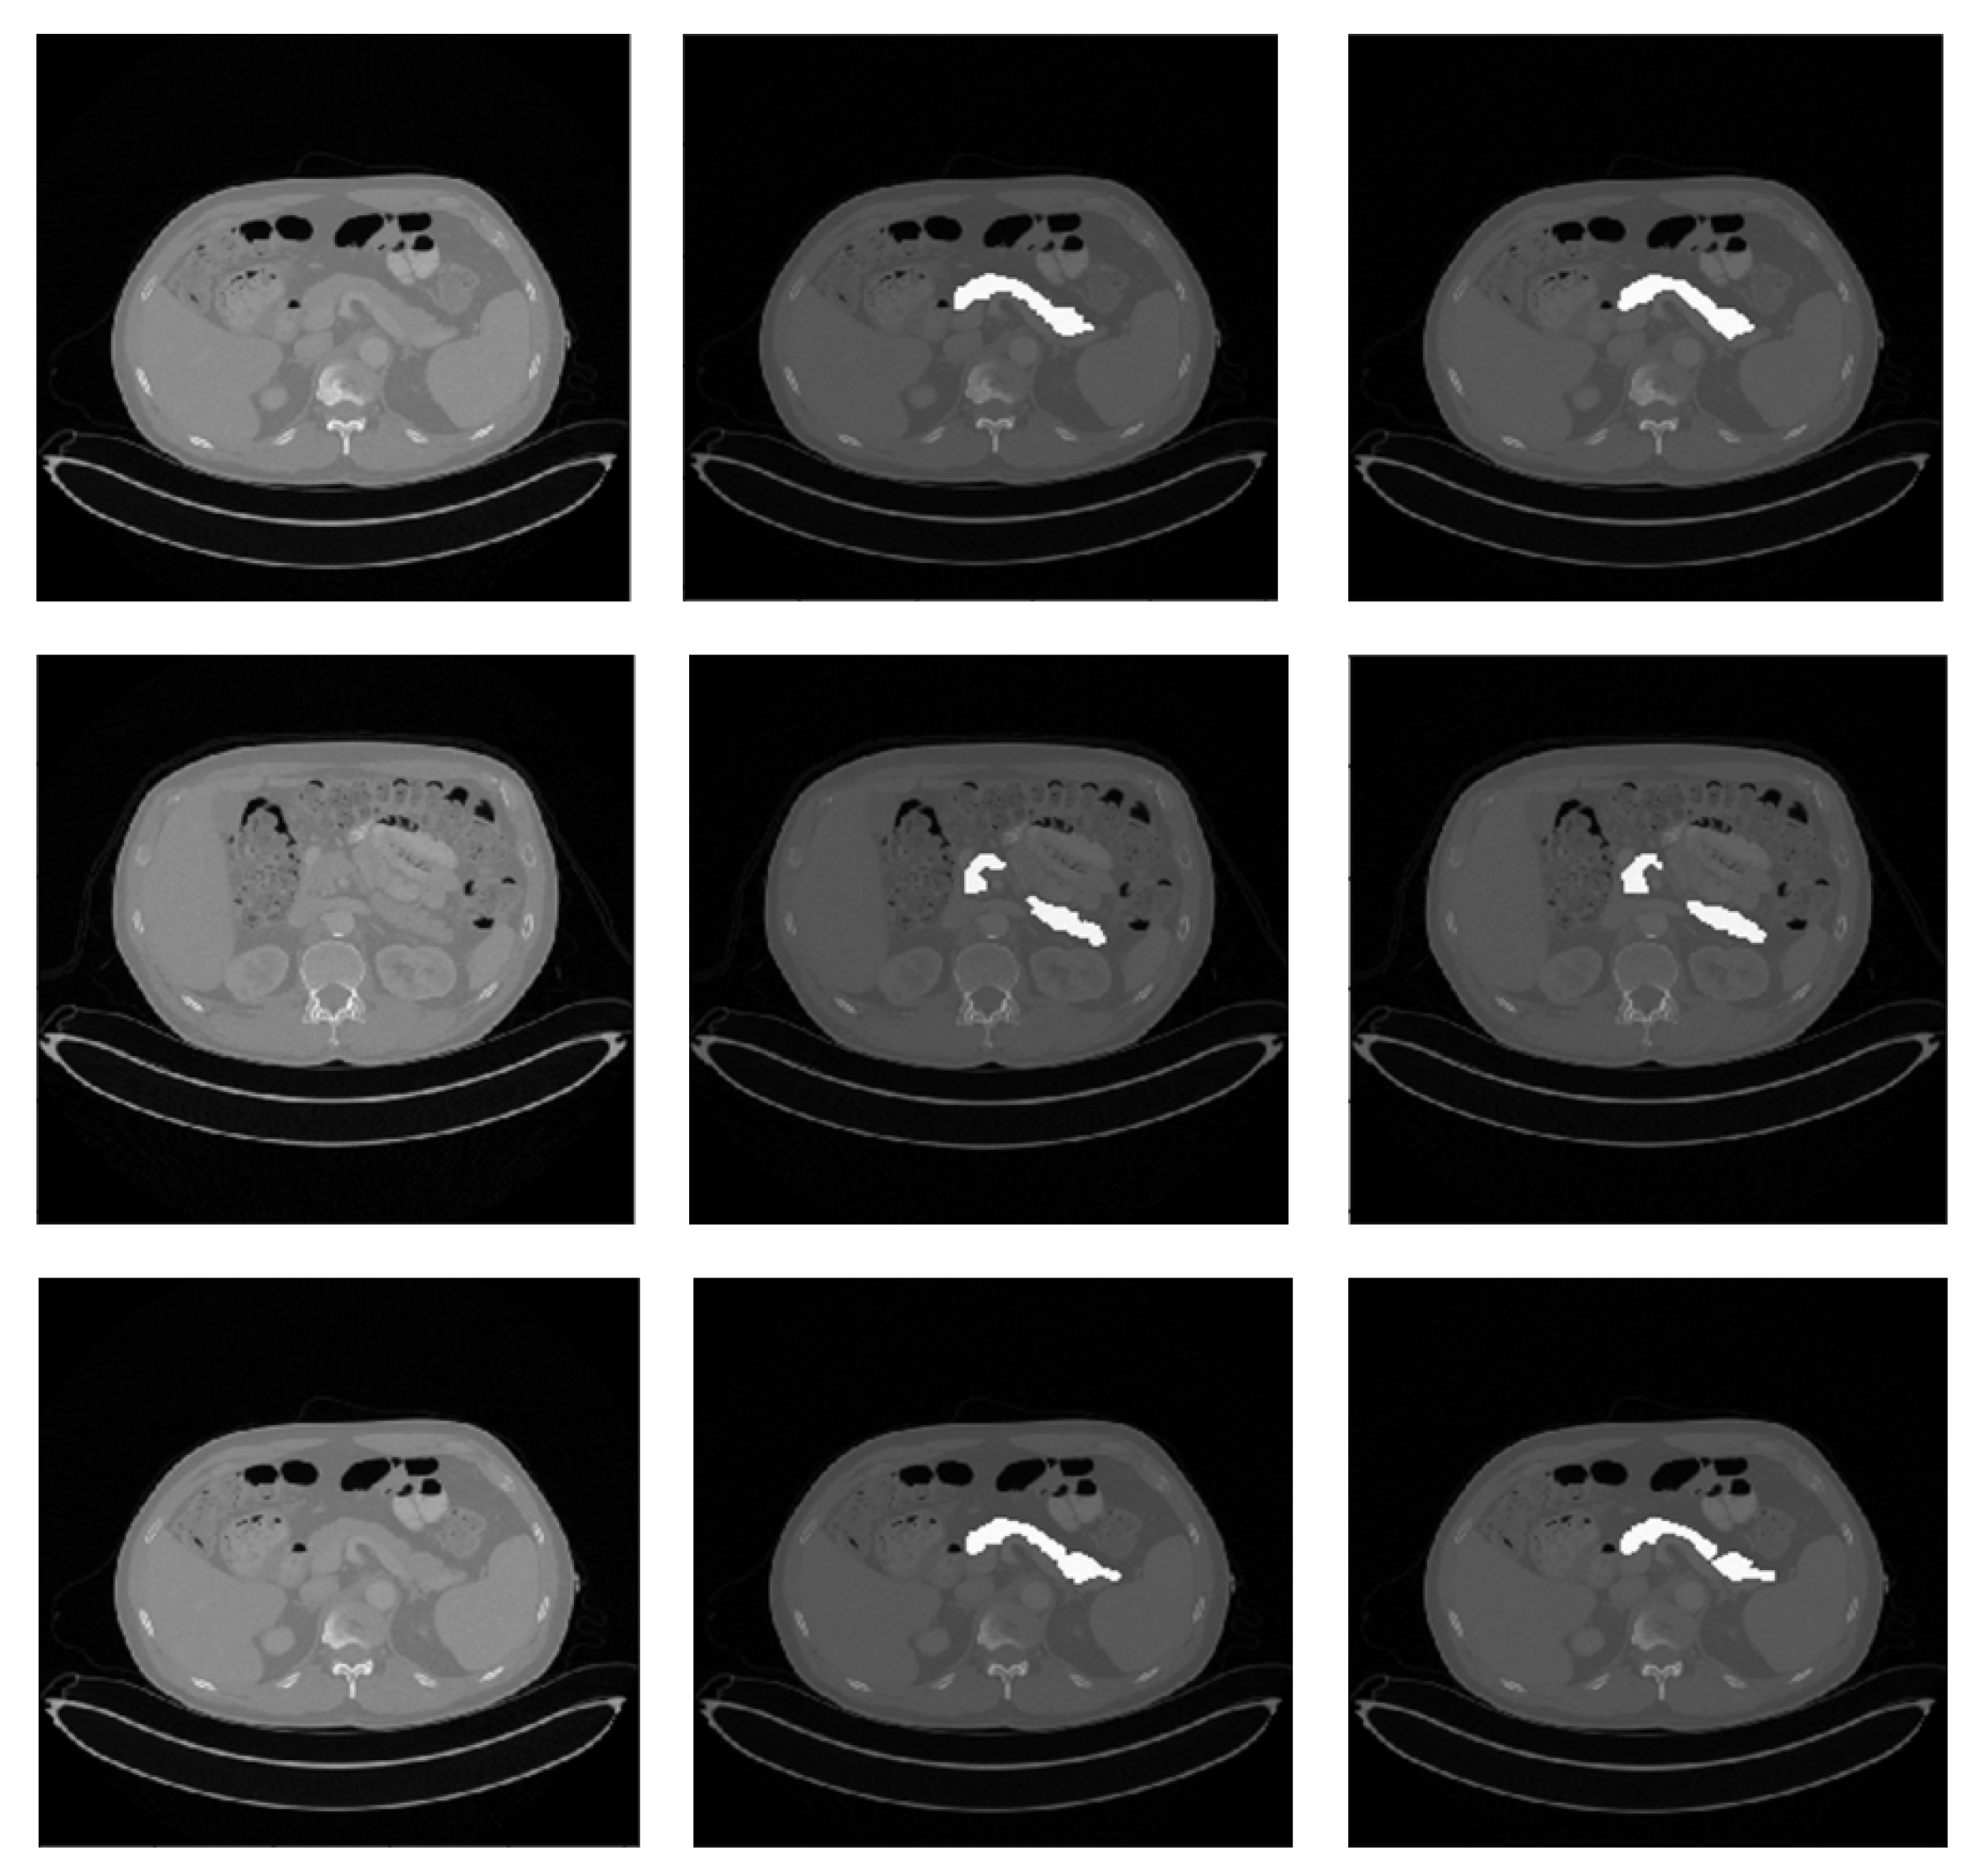

Figure 2.

Qualitative pancreas segmentation results of AX-Unet model. The images in each row arranged from left to right depicts the original image, the ground-truth segmentation, and the segmentation generated by our AX-Unet model, respectively. The segmentation results are evidently of superior quality.